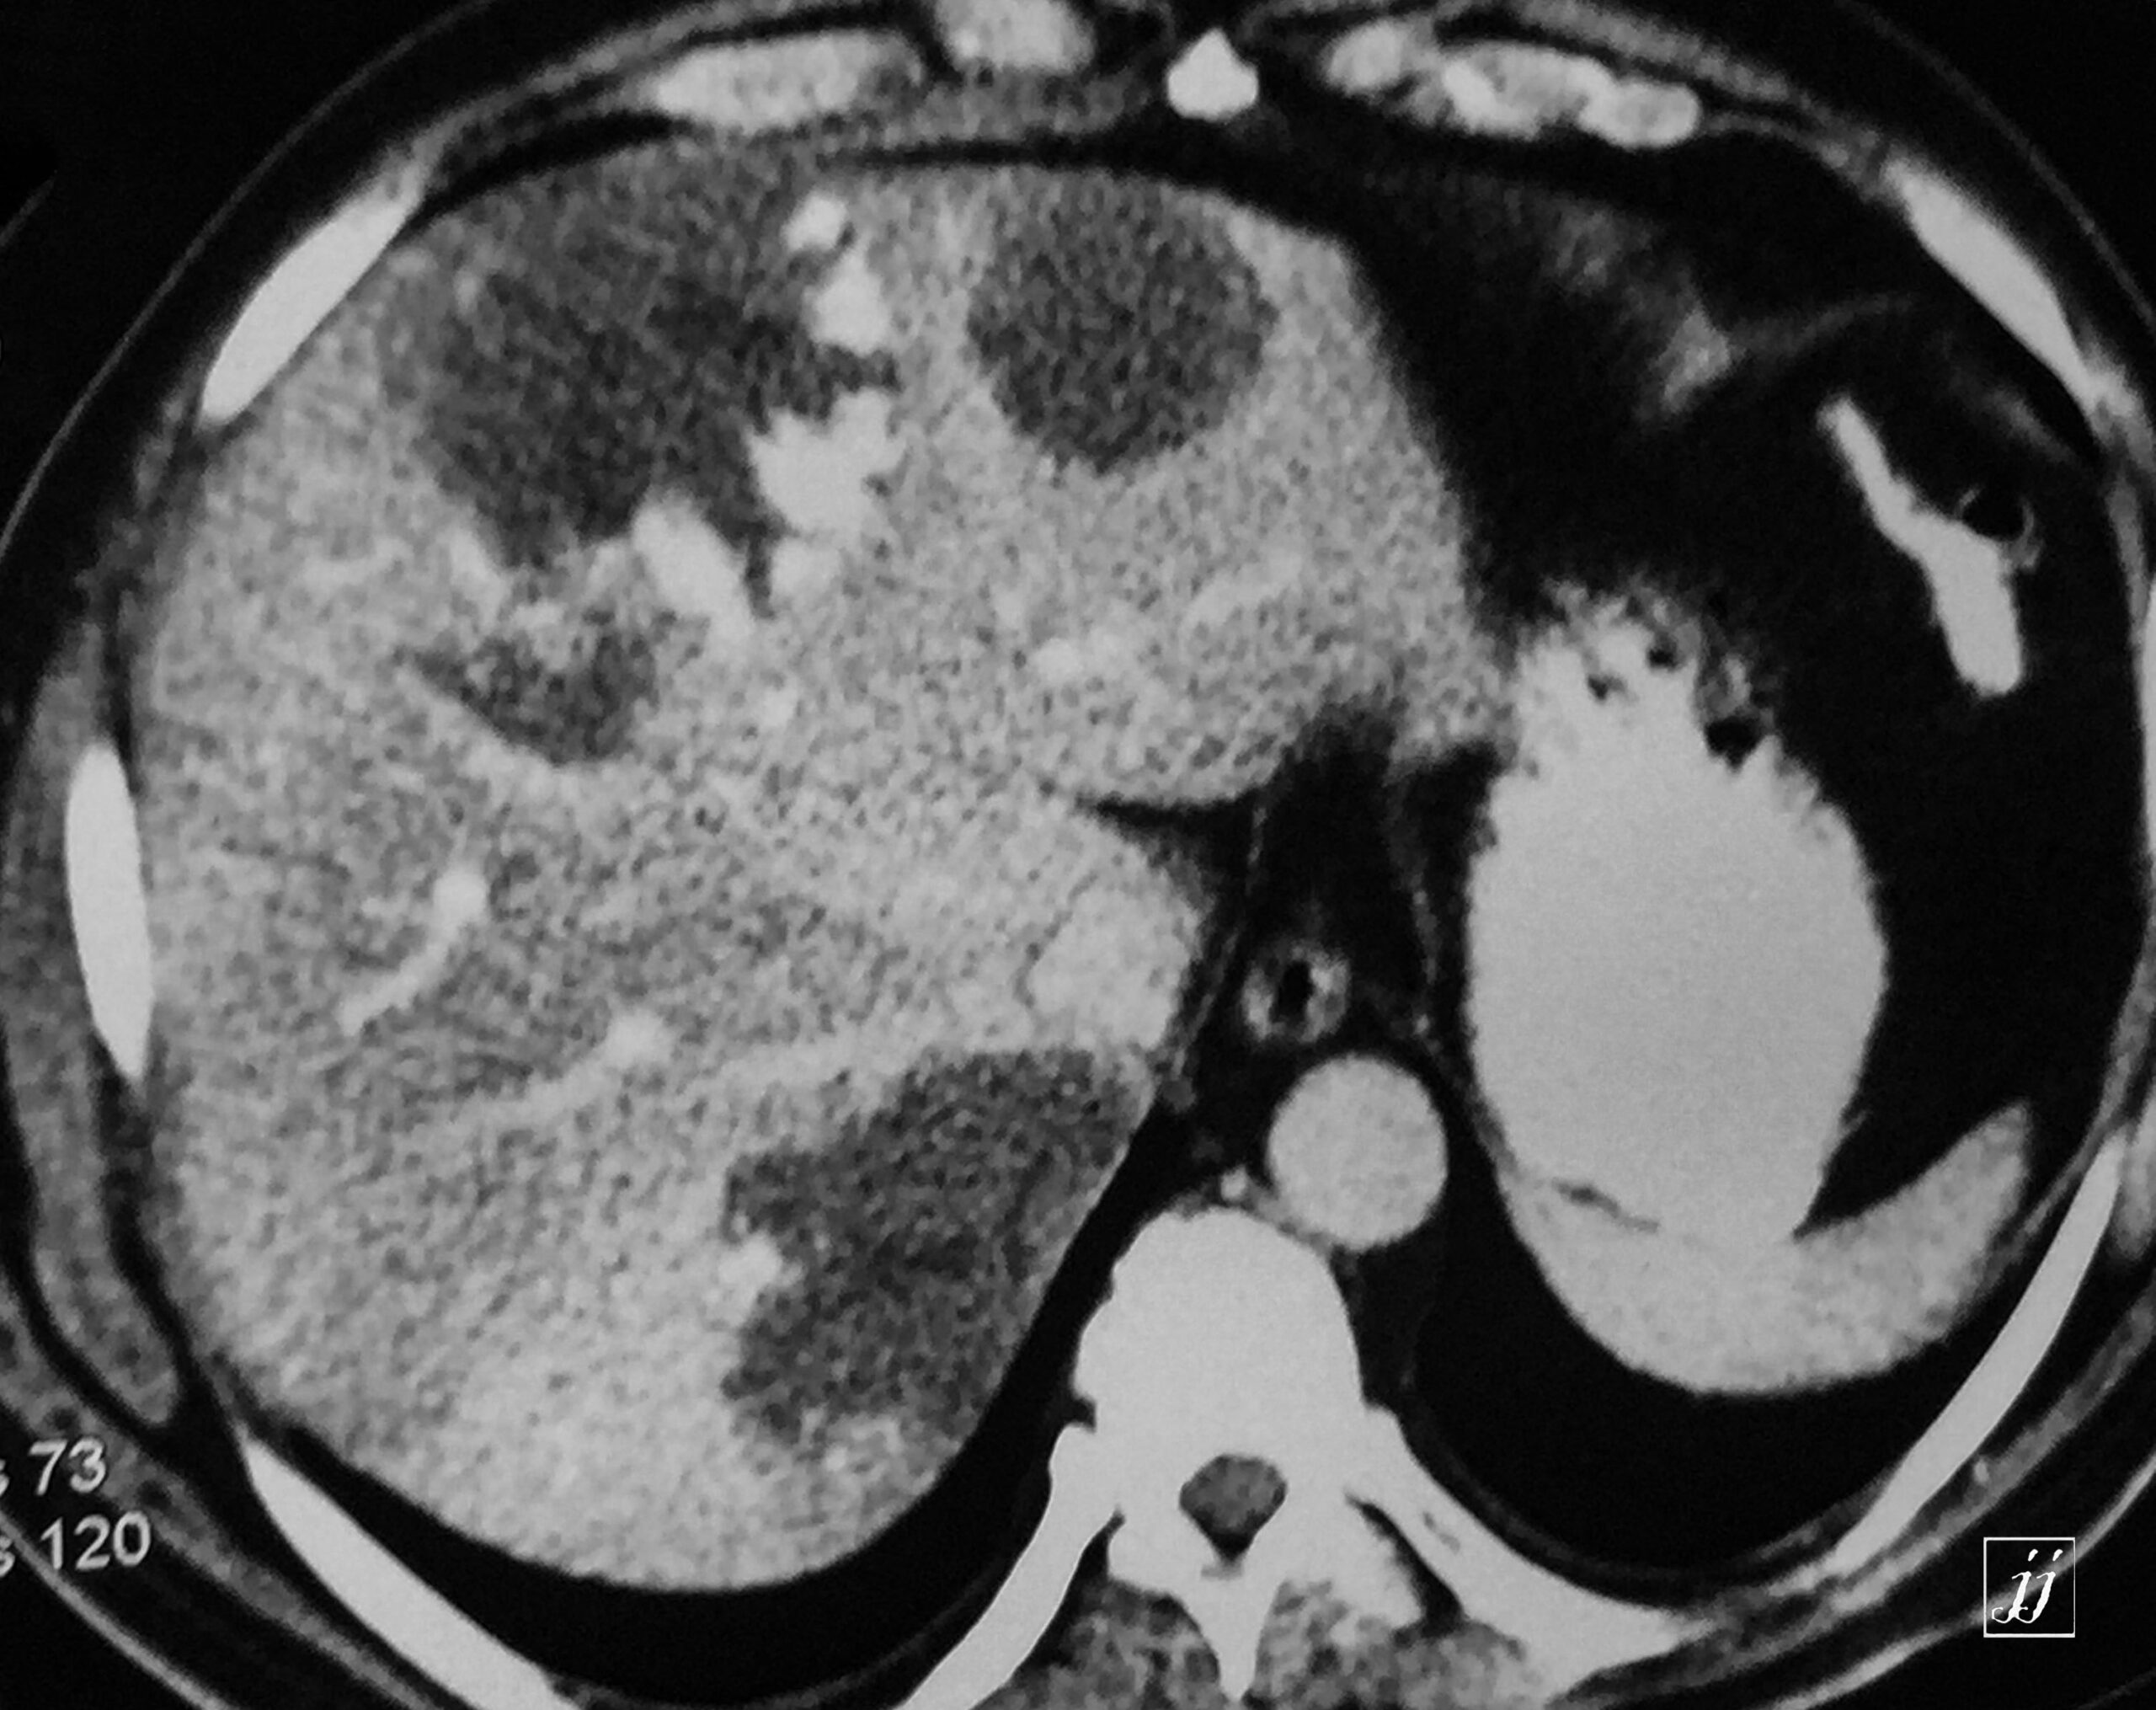

Abdomen- huge exophytic liver hemangioma with another two small hemangiomas (7)